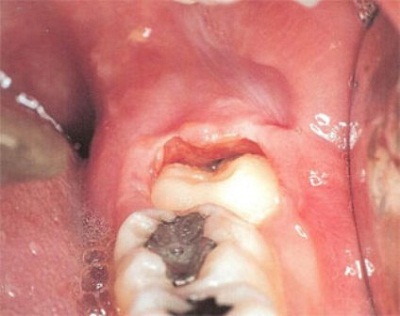

Triệu chứng sớm của việc răng khôn mọc lệch thường là những cơn đau âm ỉ. Khi răng khôn mọc đâm sang răng bên cạnh, nó sẽ làm “chiếc răng khỏe mạnh” dần bị tiêu hủy, lung lay có thể dẫn đến sâu, nặng hơn nó sẽ khiến chiếc răng này bị xô đẩy chèn ép và rụng đi.

Do răng khôn ở trong cùng của hàm nên rất khó vệ sinh, thức ăn và vi khuẩn dễ dàng tích tụ. Sự tích tụ lâu ngày gây sâu răng hoặc viêm nhiễm vùng lợi xung quanh dẫn đến sưng, đau, hôi miệng, … Bệnh viêm lợi sẽ tái phát nhiều lần nếu răng khôn không được chữa trị, những lần tái phát sau mức độ nguy hiểm càng cao. Một số truờng hợp khi những bất thường của răng khôn không được chữa trị kịp thời, nhiễm trùng lây lan sang các khu vực xung quanh như mang tai, má, mắt, cổ, ... gây nguy hiểm đến tính mạng.